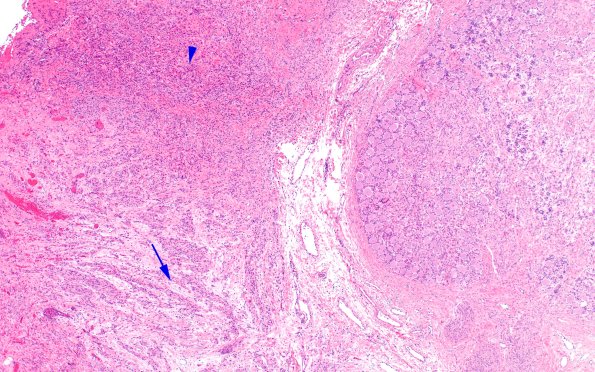

Case 14 History ---- The patient is a three month old baby girl with left brachial plexus palsy. Operative procedure: Left brachial plexus exploration and repair with sural nerve grafting. ---- 14A1 This traumatic lesion was located immediately adjacent to a DRG and consisted of mini-fascicles (arrow) and haphazard disorganized collections of neurites and Schwann cells (arrowhead). (H&E)